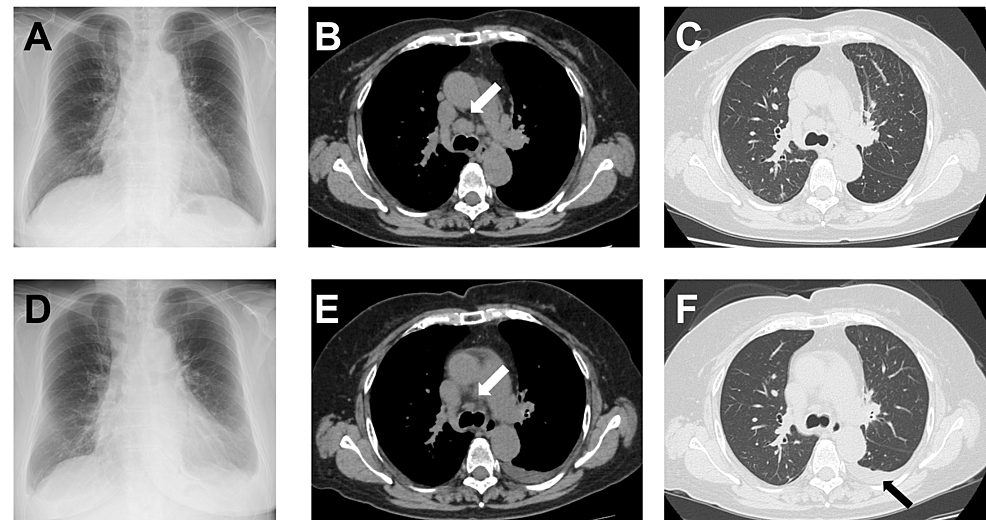

Entrectinib-Induced Heart Failure in a Patient With Metastatic Lung Adenocarcinoma: A Case Report

Entrectinib is a recently approved multikinase inhibitor to treat advanced c-ros oncogene1 (ROS1) positive non-small cell lung cancer (NSCLC). Although molecular targeted therapy is generally well tolerated, cardiovascular adverse events...

Conclusions: We presented a case of symptomatic CTRCD after entrectinib treatment in a patient with ROS1-rearranged metastatic lung adenocarcinoma. Physicians should monitor cardiac function as patients may develop heart failure, especially in the early phase of entrectinib initiation. The number of cases where entrectinib is prescribed is...